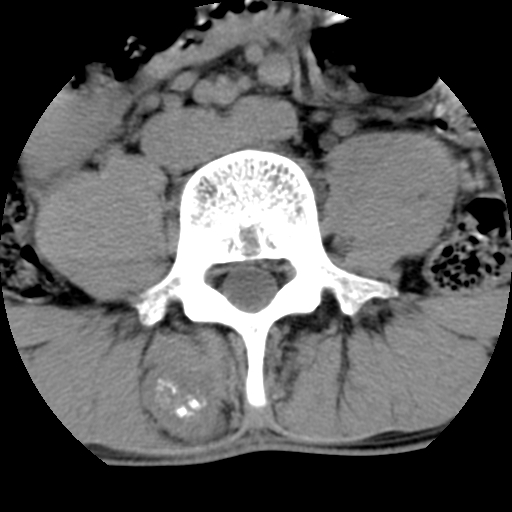

标题: CT16890:男,腰背痛.

男,腰背痛

本人诊断1tb2包虫,请会诊

1)右侧竖脊肌稍低密度肿块伴钙化(性质待定),不排除肿瘤可能;建议行进一步检查。2)腰椎间盘突出。

1.右侧竖脊肌软组织肿块伴团块状钙化,首先考虑血管瘤可能性大;建议行进一步检查;2。腰椎间盘突出。

软骨肉瘤可能性大